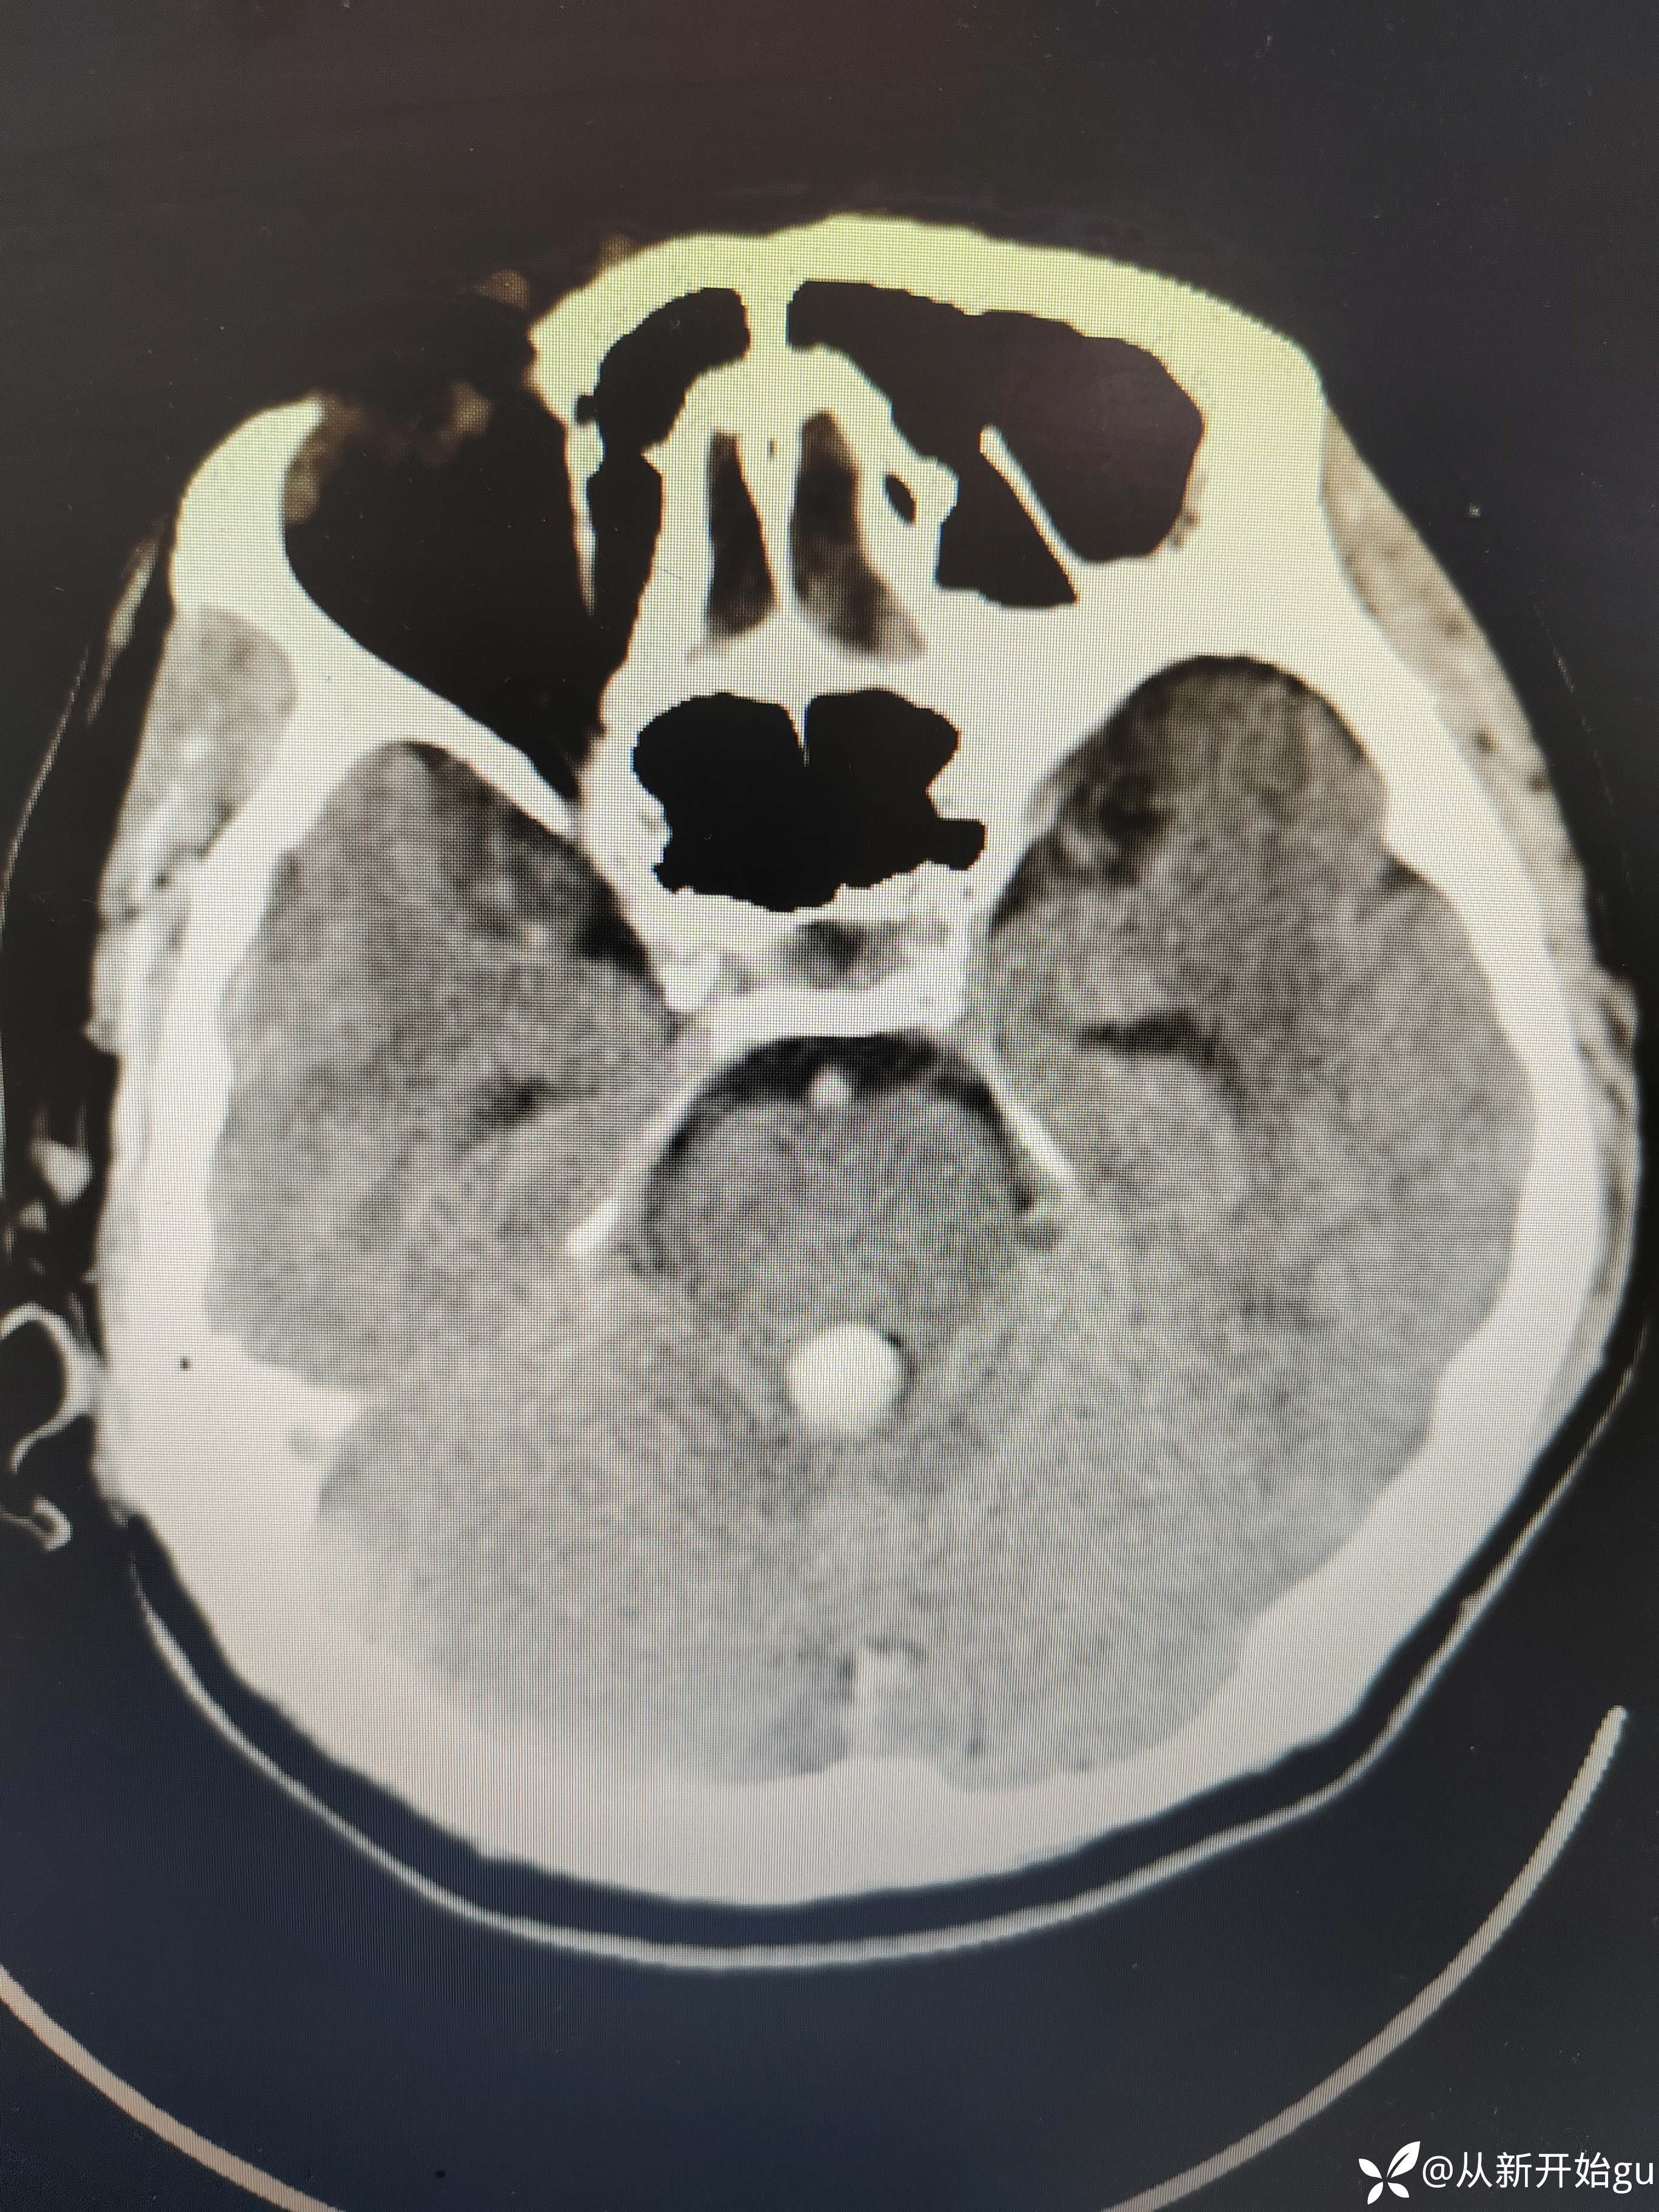

【检查】:完善颅脑CT.

【检查】:完善颅脑CT.